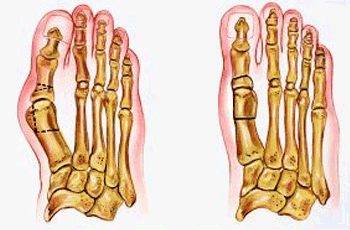

TÉCNICA QUIRURGICA